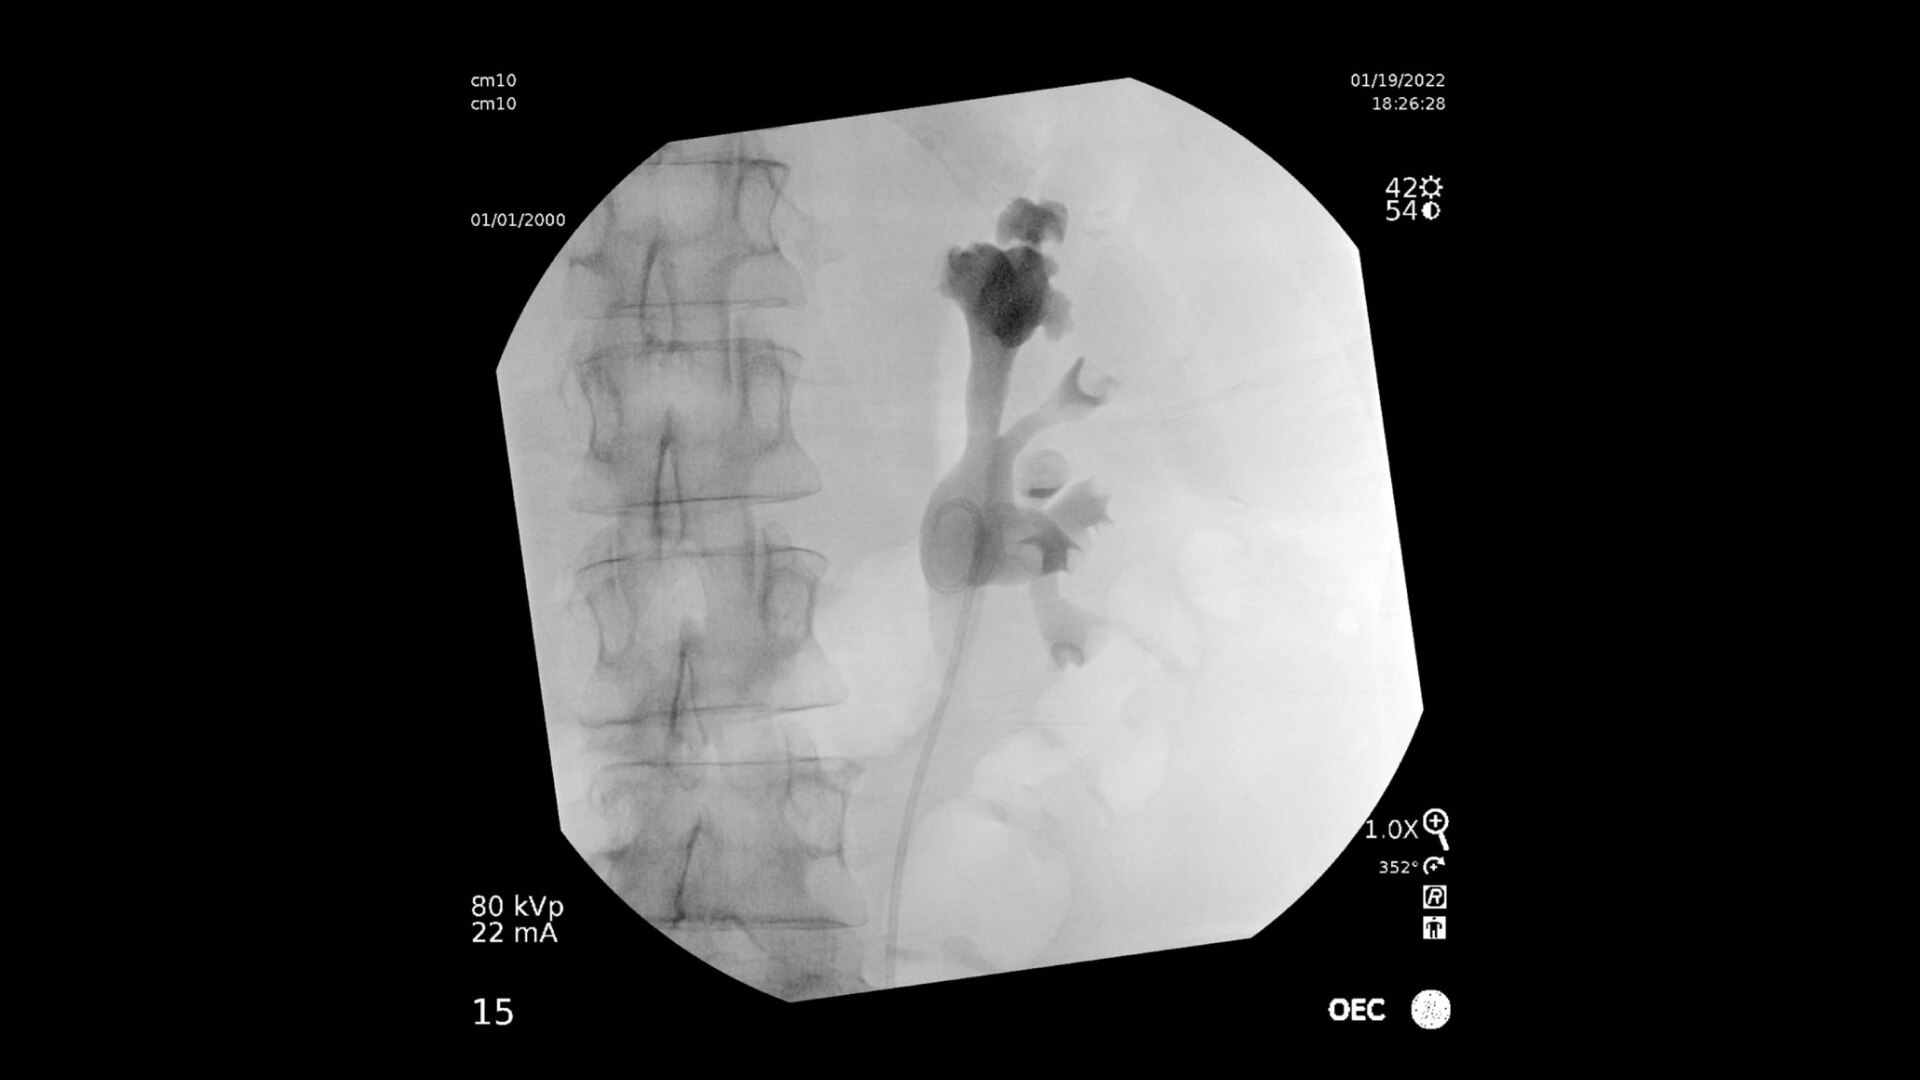

OEC mobile C-arms deliver incredible image quality and large field of view for comprehensive visualization of the urinary anatomy. The streamlined design provides more access and flexibility for an optimal urology suite set up.

Clearly visualize the entire urinary tract from the kidneys to the bladder during urology procedures. OEC C arms deliver amazing image quality allowing interventionalists to easily identify small details of urinary anatomy, such as urological cavities. A clear display with large field of view provides comprehensive visualization without need for repositioning an OEC C-arm, enabling an effortless workflow

Detail displayed 1 for 1 from detector to a 4K UHD display for stunning image quality and visualization of low density drainage tubes and thin biopsy brushes.

The General HD preset profile optimizes to present high contrast, enhanced edge images to optimally see small detail such as stones in pancreatic duct.

Urology imaging you need

Complex urology procedures require powerful imaging systems.

OEC premium C-arms perform in a variety of procedures such as:

• Intravenous pyelography

• Retrograde pyelogram

• Percutaneous nephrolithotomy